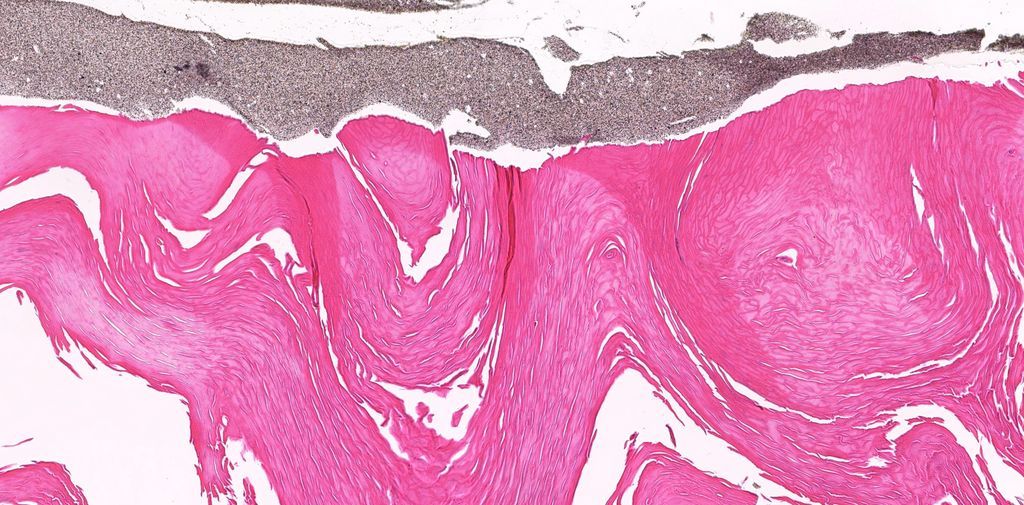

20 yo F. Bilateral groin excisions. Diagnosis? Digital slides: kikoxp.com/posts/8027 Answer ✅ youtu.be/Zy07nO1VuiY?si… #pathology #pathologists #pathTwitter #dermpath #dermatology #dermatologia #dermtwitter

20 yo F. Bilateral groin excisions. Diagnosis?

Digital slides: kikoxp.com/posts/8027

Answer ✅ youtu.be/Zy07nO1VuiY?si…

#pathology #pathologists #pathTwitter #dermpath #dermatology #dermatologia #dermtwitter